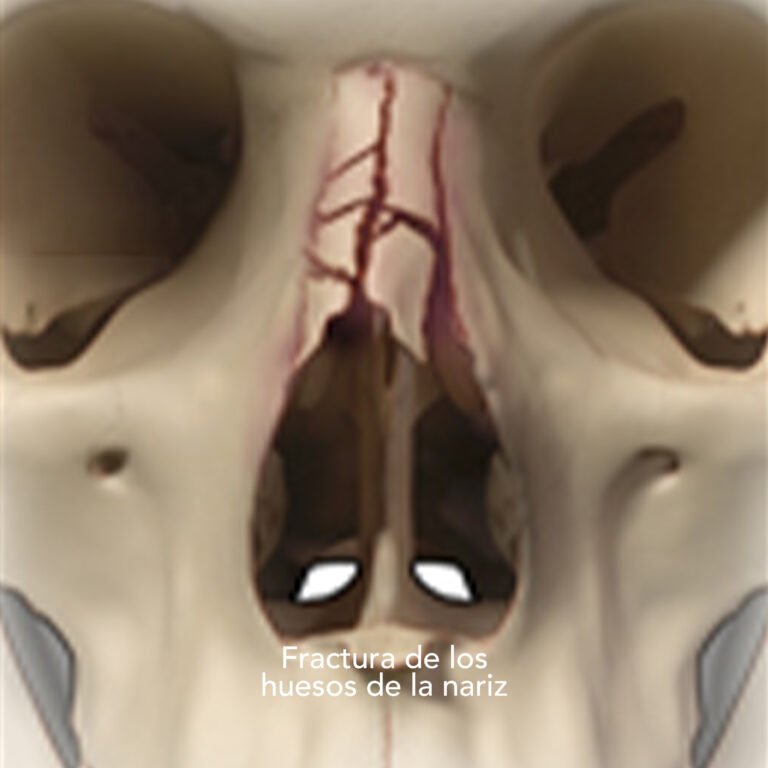

Fractura nasal o de nariz

Es una lesión en los huesos de la nariz causada por un golpe o caída, que puede provocar dolor, sangrado, deformidad y dificultad para respirar.

¿Cómo se trata?

El tratamiento depende del tipo de fractura:

• Reducción cerrada: reposicionamiento manual de los huesos sin cirugía si la lesión es reciente.

• Cirugía: se corrige la estructura nasal cuando la fractura es más compleja o afecta la respiración.